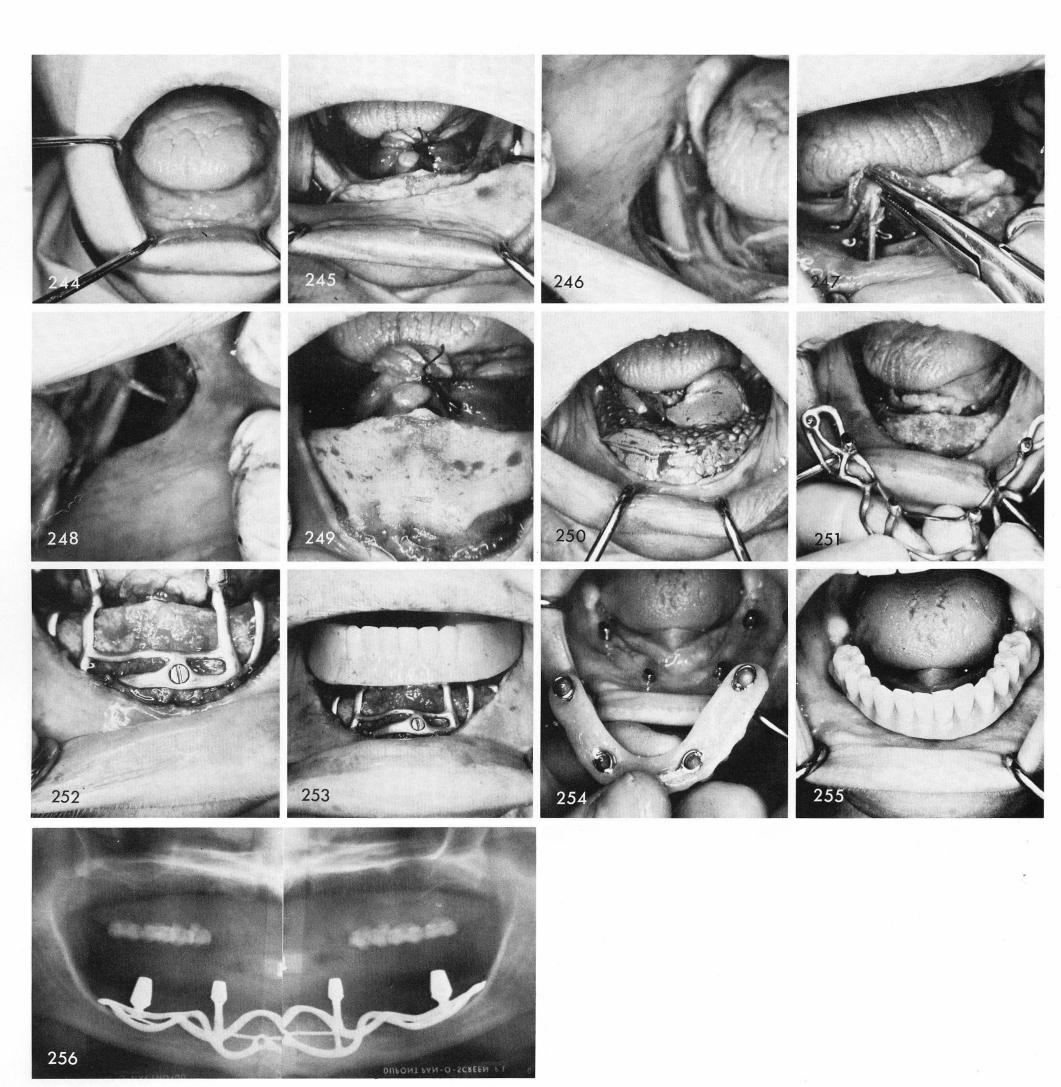

Fig. 244 reveals a severely resorbed mandible, with underlying nerve exposures, figs. 245, 246, 247, 248. Enough bone still exists anteriorly, fig. 249. After covering the nerves with tin foil an impression is taken, fig. 250, for the casting of the implant, fig. 251, which was screwed into position, fig. 252. The temporary stent is tried in, fig. 253, and the final prosthesis completed after sufficient healing had taken place, figs. 254, 255. The x-ray, fig. 256. The design of this implant was made not to cross over the nerve bundles.

1 Nerves covered with tin foil and mandibular impression taken